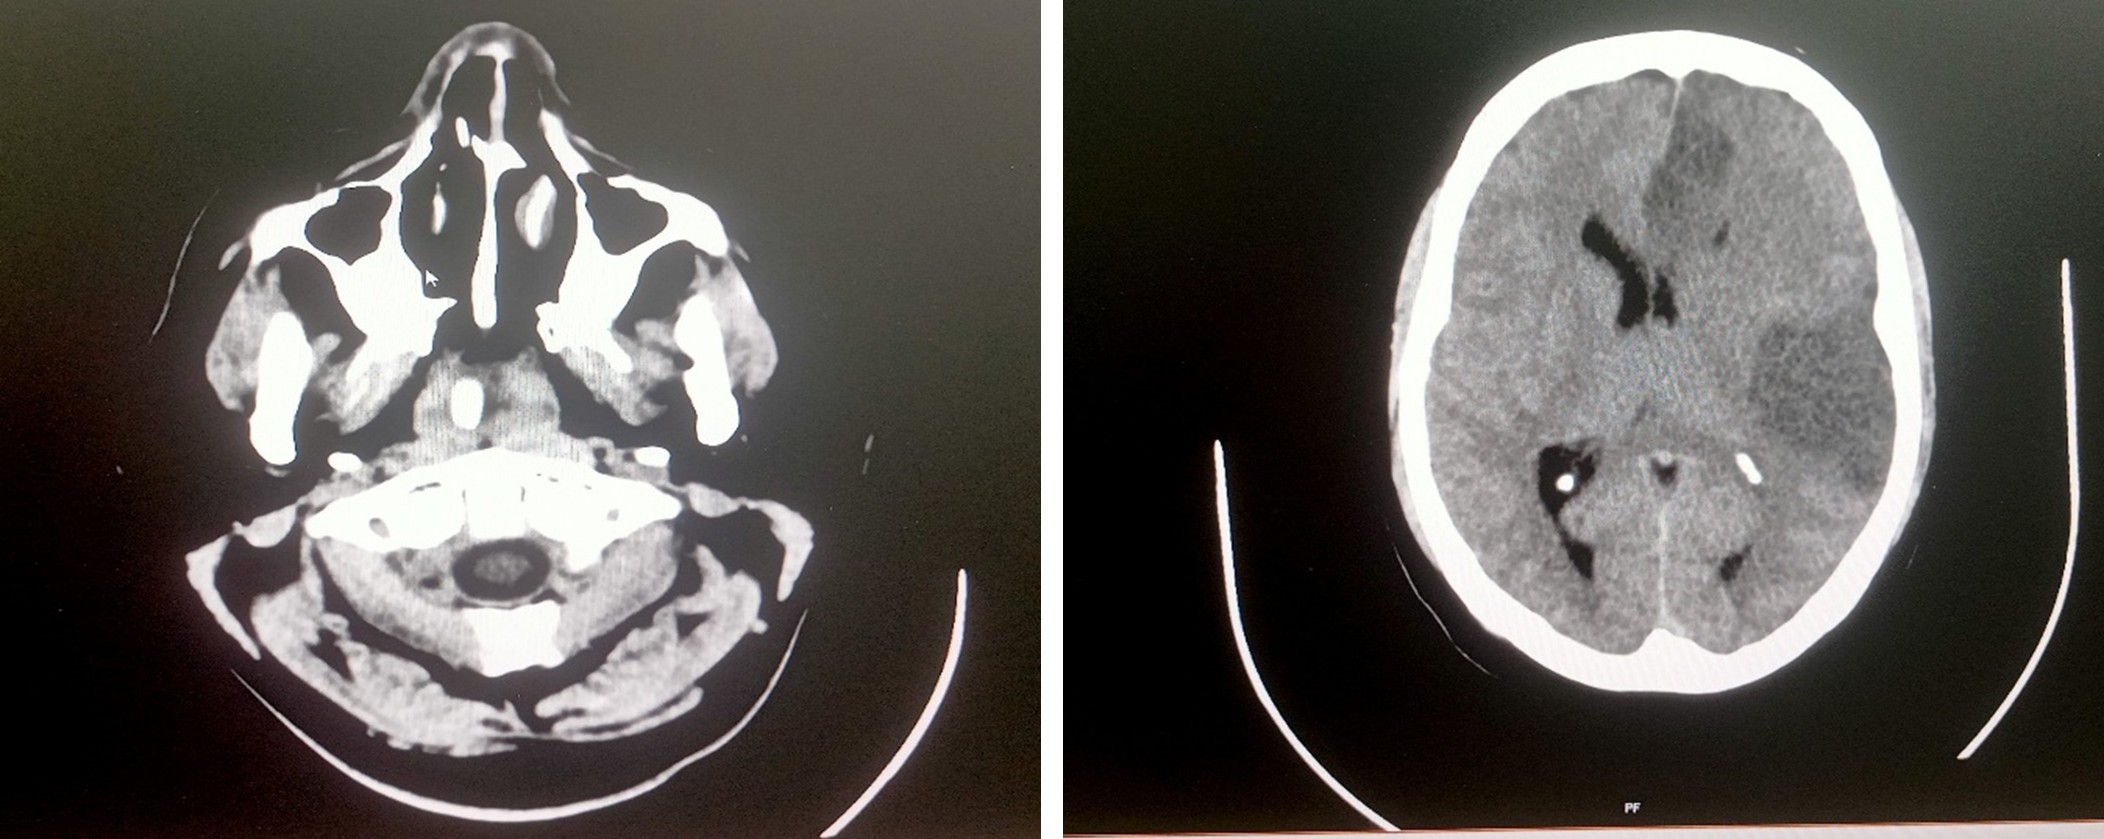

MRI of brain screening – Report 17.06.2025

The acute infarct left MCA territory with minimal mass effect

Multislice CT scan brain plain study – 17.06.2025

Acute infarct in left temporo – parietal cortex with minimal mass effect

Multislice CT scan brain plain study – 18.06.2025

Acute infarct in left MCA and ACA territory with mass effect and midline shift

Multislice CT scan brain plain study – 23.06.2025

Postoperative bony defect left fronto – temporo – parietal region with infarct in left MCA and ACA territory with minimal mass effect

Multislice CT scan brain plain study – 24.06.2025

K/c/o Left ACA and MCA territory infarct status post craniectomy, on follow-up

Subacute infarct with hemorrhagic transformation seen in left frontal parietal and temporal lobes

- Malignant Middle Cerebral Artery (MCA) infarct and surgical decompression: Pre-op and post-op CT brain findings